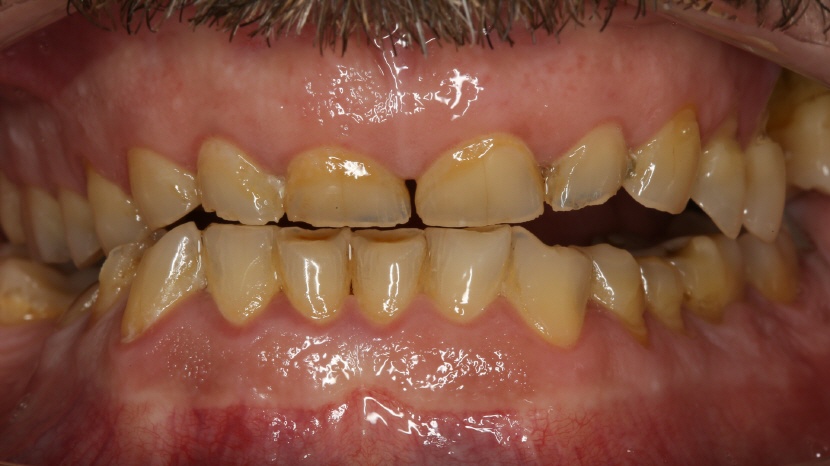

Patienten Fall 1:

• Lippenbild vor Therapiebeginn

Der Patient wünscht eine Verbesserung der Ästhetik. Er stört sich an der Farbe und Form seiner Zähne und wünscht möglichst helle und längere (inkakte) Zähne.

• Übersichtsbild

Deutlicher Substanzverlust aufgrund von Abrasion (Abnutzung) und Erosion (Säureeinwirkung). Zusätzlich fehlen im Unterkiefer rechts und Oberkiefer links je ein Molar (Stockzahn).